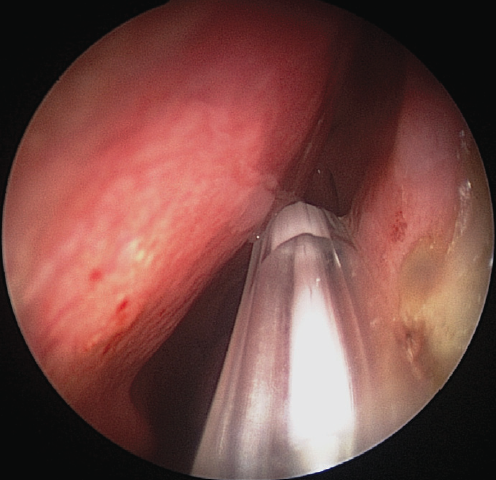

The intervention was performed as follows. Under local and conduction anesthesia with intravenous sedation, antegrade probing of the dacryostomy area was performed with the formation of an opening in the scar tissue (in three cases) and with probing of residual dacryostomy (in three cases; Fig. 2). Purulent discharge was removed from the lacrimal sac cavity using an aspirator. A balloon was inserted endonasally into the dacryostomy opening using a curved von Eicken cannula for irrigation with an outer diameter of 4.0 mm and length of 15 cm (Karl Storz, Germany; Fig. 3). Balloon dacryoplasty was performed according to the protocol we developed earlier in the experiment [8] and tested in the clinical setting (Fig. 4) [9]. The balloon was dilated at a pressure of 8 atm. for 90 s, and after 10 s, it was repeated for 60 s. After deflation, the balloon was removed. Figure 5 shows an enlarged dacryostomy after the intervention. A hemostatic sponge was inserted into the dacryostomy area, which was removed 48 h after the surgery.

Fig. 2. Endoscopic view of scar tissue in the area of dacryostoma (left nasal cavity). The ostium was probed with Bowman probe

Рис. 2. Эндоскопическая картина области рубцово-изменнённой дакриостомы (левая половина носа). Зонд Боумена выведен через дакриостому